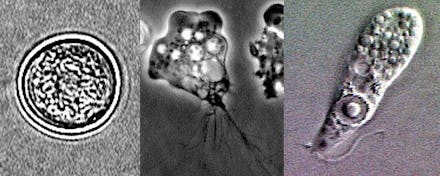

Naegleria fowleri, commonly referred to as the "brain-eating amoeba," lives off bacteria found in sediment at the bottom of lakes and rivers, but it can sometimes rise closer to the surface and infect humans, according to the Centers for Disease Control and Prevention. It's most commonly encountered in the southern United States during the summer, when temperatures are highest, the CDC reports.

The amoeba often enters the body through a person's nose. Once inside, it travels to the brain, where it causes an infection known as primary amoebic meningoencephalitis, or PAM.